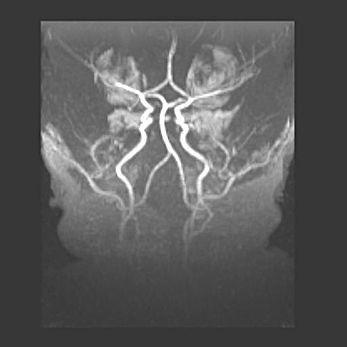

Подострая гематома правой гемисферы мозжечка.

Наружная гидроцефалия.

Возраст: 15 дней

Вес: 3100 г

Пол: женский

Окружность головы: 37 см

Срок гестации: 35-36 недель

При открытой наружной форме гидроцефалии у новорожденных расширяются и переполняются субарахноидные пространства.

Кровоизлияния в мозжечок имеют две клинико-анатомические формы: полушарные гематомы и кровоизлияния в червь.

К появлению этой патологии может привести: повреждения головного мозга, возникающие в результате асфиксии и гипоксии плода при беременности, или травмы во время родов. Редко гематома мозжечка может быть результатом первичной коагулопатии и сосудистой мальформации, диссеминированном внутрисосудистом свертывании, изоиммунной тромбоцитопении.